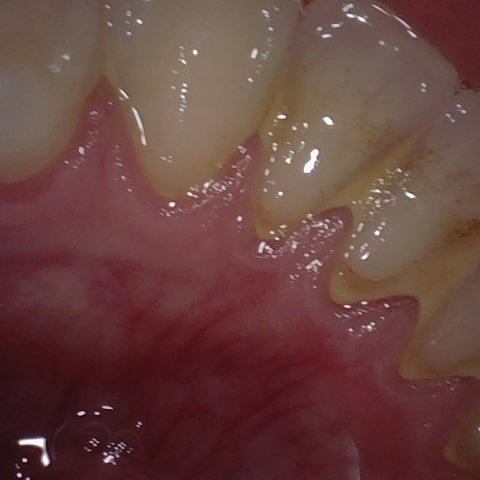

Annotated as "Good"

Original Image Rendering Image